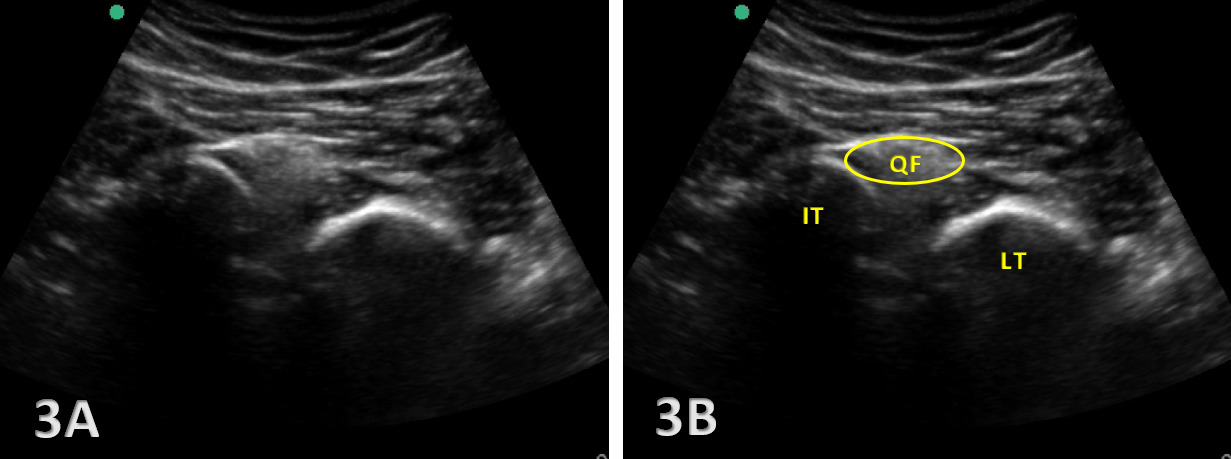

The ischiofemoral space (IFS) is the anatomical interval between the lateral cortex of the ischial tuberosity and the medial cortex of the lesser trochanter of the femur. Within this space lies the quadratus femoris muscle, along with the sciatic nerve and associated vascular structures, all of which are crucial to hip function. Narrowing of the IFS, typically defined as a distance below 1.5 cm, can lead to IFI, a condition characterized by pain and restricted motion in the posterior hip. In addition to the IFS, the quadratus femoris space (QFS)the distance between the hamstring origin on the ischial tuberosity and the insertion of the quadratus femoris muscle—is another critical measurement in assessing IFI.

When the IFS becomes narrowed, compression of the quadratus femoris muscle and the sciatic nerve can occur, leading to the hallmark symptoms of IFI, including deep posterior hip pain and potential nerve-related symptoms. Normal IFS values range from 2 to 2.5 cm, and accurate measurement of this space is crucial for diagnosis. Given that the actual space is highly variable based on the gait cycle or what position the hip is in during testing, and MRI tends to overestimate the measurement,6 MSKUS is the perfect tool for assessing this space either statically or dynamically. Dynamic hip MSKUS can corroborate IFI and space with the change in position of the lower extremity, as well as to assess whether the symptoms are due to other potential causes.7 MSKUS is an invaluable tool for visualizing these structures, offering dynamic, real-time imaging that enhances diagnostic accuracy in cases of suspected IFI .

Narrowing of the IFS: A key indicator of IFI is the decreased distance between the ischial tuberosity and the lesser trochanter. Ultrasound allows for precise measurement of the IFS, particularly at the point of greatest narrowing, which is critical for diagnosing impingement. IFS measurements by MSKUS have been shown to be very similar to those obtained with MRI.15

Quadratus Femoris Edema or Atrophy: MSKUS can identify increased echogenicity in the quadratus femoris muscle, which suggests edema or early degeneration. This muscle is most involved in IFI and serves as a crucial diagnostic marker.

Dynamic Testing: One of the strengths of MSKUS is its ability to assess the IFS during hip movement, such as extension and external rotation. This real-time imaging allows clinicians to directly observe impingement of the quadratus femoris during dynamic motion, further aiding in diagnosis.